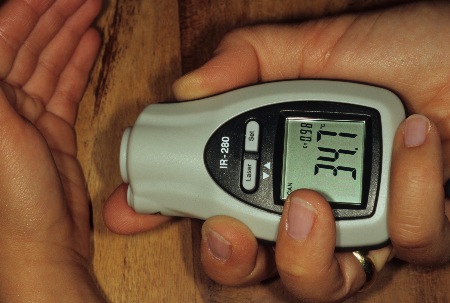

Stromquelle für Elektrotherapie

Stromquelle für Elektrotherapie